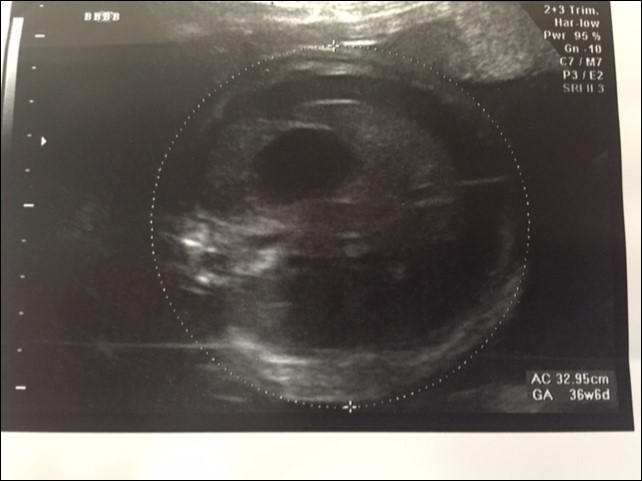

A 37 year old G3P2 female was referred to the pediatric surgical clinic for a twin pregnancy with one of the twins having a large left sided lung mass. The mother had a BMI of 48 and had undergone lap band surgery in the past. The lung mass was detected at 22nd week of gestation and was noted to be homogenous and solid on ultrasound and had a Cyst Volume Ratio (CVR) of 1.4. The twins were dichorionic diamniotic. Twin A had a posterior placenta and twin B (twin with the lung mass) had an anterior placenta. The lesion was located in the left hemi thorax and did not have any associated pleural effusion at first. The differential diagnosis for this lesion included a Stoker Type3 CPAM, a mediastinal teratoma, and a diaphragmatic hernia6. The Twin B was superior in the uterus in a breech position to the right side with a vertical pocket of amniotic fluid measurement of 6.8cm. The Bio Physical Profile score was 10/10. While the middle cerebral artery and ductus venosus dopplers were normal, there was some drop off in the end diastolic flow in the umbilical artery Dopplers. The mother was placed on weekly hi-definition ultrasound follow ups. Echocardiogram showed no structural cardiac defect. Steroids (betamethasone 12mg IM, two doses, 24hours apart) were administered after the development of pleural effusion was noted at the repeat ultrasound performed at 24 weeks and at this point CVR had increased to 1.6. As there was an inadequate response to steroid administration, with the development of a mediastinal shift from the mass effect of the lesion and significant pleural effusion, aspiration of the pleural fluid was performed twice (at weekly intervals during the 26th and 27th week of gestation) with recurrence of the effusion. The pleural fluid analysis showed that it was transudate on both occasions. The volume aspirated on each occasion was about 20 ml. Ascites was also detected and 10 ml of abdominal fluid was aspirated during the second aspiration. It appeared that the fetus was developing hydrops. During the 30th week ultrasound showed a significant mediastinal shift to the right, a large liver with ascites, and increased fetal skin thickness. A thoraco-amniotic shunt was placed at the 30th week of gestation and another course of steroids administered Figure 1 and Figure 2. The significant maternal subcutaneous fat would allow only a direct lateral access into the pleural cavity. The twin and mother were doing well with no symptoms. However, three weeks later, the fetus was able to dislodge the 'double-J' catheter and a second thoraco-amniotic shunt was placed because of recurrence of pleural effusion. While this was successful initially, the combination of the twin pregnancy and interventions led to premature delivery of the twins at 34 weeks gestation. MRI was not considered in the evaluation because of the large BMI.